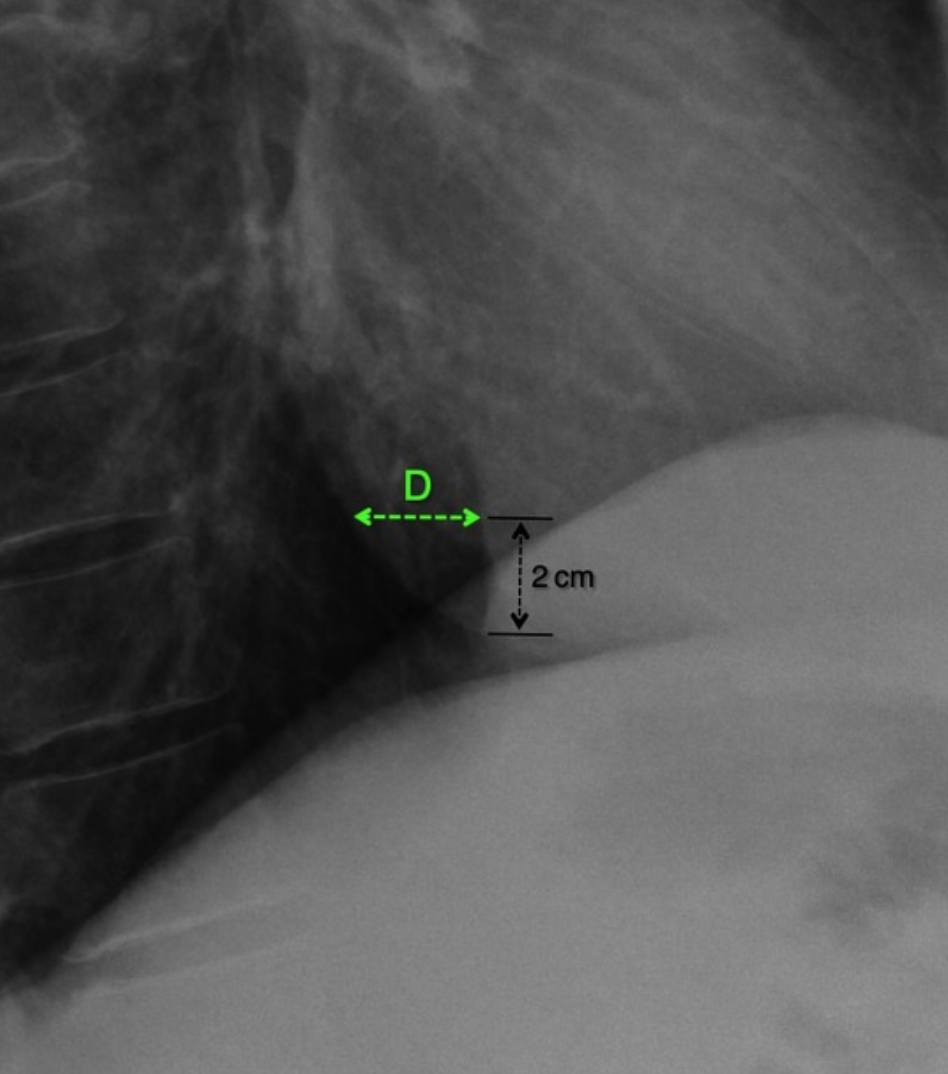

Hoffman-Rigler Sign

• Seen in LV hypertrophy

• Only seen on lateral radiograph and measured 2 cm above the intersection of IVC and diaphragm

• Distance between the LV border and posterior border of IVC is >2.8cm